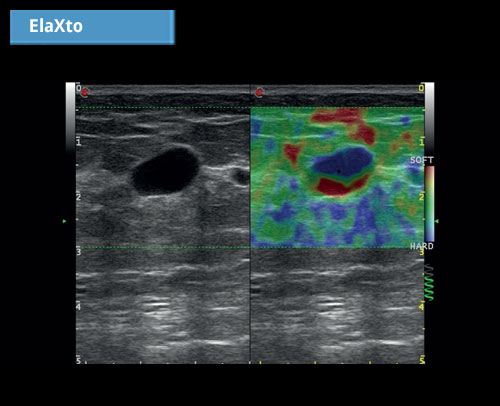

ElaXto: ElaXto je neinvazivní metoda, která pomáhá lékařům při hodnocení elasticity tkáně. Rozdíly v tkáňových reakcích jsou detekovány a vizualizovány v reálném čase.